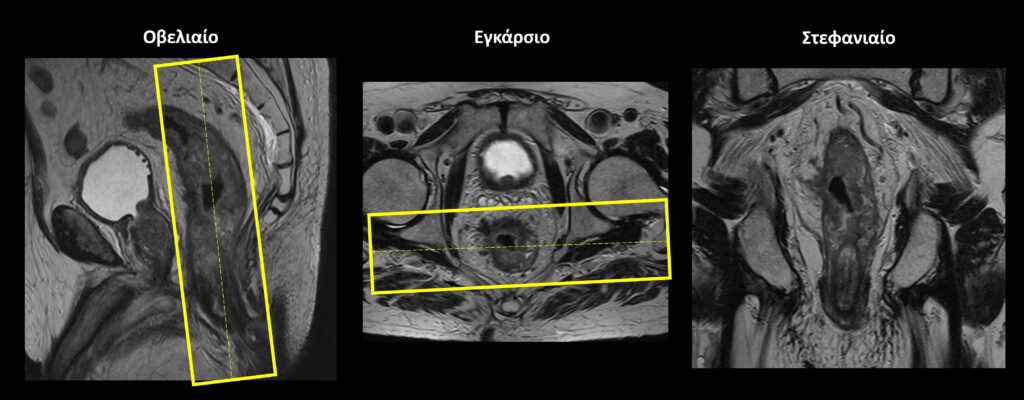

Οβελιαίο επίπεδο (Sagittal): οι οβελιαίες τομές σχεδιάζονται παράλληλα με το ορθό και τον πρωκτικό σωλήνα τόσο στο εγκάρσιο όσο και στο στεφανιαίο επίπεδο. Οι τομές πρέπει να περιλαμβάνουν ολόκληρο το ορθό και το σιγμοειδές από τα δεξιά έως τα αριστερά.

Εγκάρσιο (Axial/Transversal): οι εγκάρσιες τομές σχεδιάζονται κάθετα σε οποιονδήποτε ορατό όγκο εντός του ορθού, τόσο στο οβελιαίο όσο και το στεφανιαίο επίπεδο. Ο αριθμός των τομών προσαρμόζεται ώστε να καλύπτεται επαρκώς ολόκληρος ο όγκος. Εφόσον δεν υπάρχει κάποιος ορατός όγκος, οι εγκάρσιες τομές σχεδιάζονται κάθετα στο ορθό τόσο στο οβελιαίο όσο και το στεφανιαίο επίπεδο. Σε περιπτώσεις μη ορατού όγκου, οι τομές πρέπει να περιλαμβάνουν ολόκληρο το ορθό, από την ορθοσιγμοειδή συμβολή (πάνω)έως και την ορθοπρωκτική συμβολή (κάτω).

Στεφανιαίο (Coronal):οι στεφανιαίες τομές σχεδιάζονται παράλληλα με οποιονδήποτε ορατό όγκο εντός του ορθού, τόσο στο οβελιαίο όσο και το εγκάρσιο επίπεδο. Ο αριθμός των τομών προσαρμόζεται ώστε να καλύπτεται επαρκώς ολόκληρος ο όγκος. Εφόσον δεν υπάρχει κάποιος ορατός όγκος, οι στεφανιαίες τομές σχεδιάζονται παράλληλα με το ορθό τόσο στο οβελιαίο όσο και το εγκάρσιο επίπεδο. Σε περιπτώσεις μη ορατού όγκου, οι τομές πρέπει να περιλαμβάνουν ολόκληρο το ορθό, από μπροστά έως πίσω.